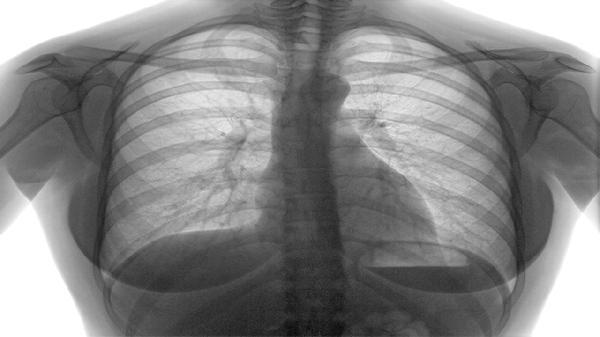

癌细胞扩散至脑部可压迫视觉中枢或动眼神经,导致眼球运动异常及凝视表现。常见于肺癌、乳腺癌等易发生脑转移的癌种,伴随头痛、呕吐等症状。需通过头颅核磁共振确诊,采用脱水降颅压药物或放射治疗缓解。